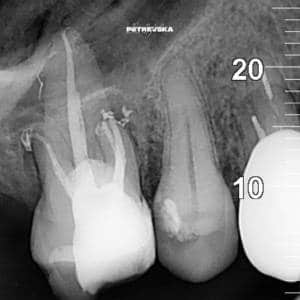

Најчесто забот е веќе „умртвен“, па оваа процедура е безболна и нема потреба од анестезија. Но, кога при некои дијагнози делови од нервот се сепак осетливи, процедурата се изведува со локална анестезија и е безболна. Каналите на коренот на забот треба механички и хемиски да се исчистат и дезинфицираат, а потоа прецизно (до дел од милиметар), да се наполнат со трајно ендодонтско полнење.

Во  ВЕГА, за ендодонтски третман на забите користиме неколку современи системи за работа, кои вклучуваат апаратура специјализирана за таа намена . Со неа, со извонредна прецизност (во дел од милиметарот) ја мериме должината на коренските канали. Истите ги дезинфицираме и овозможуваме успешно лекување и непречено функционирање на „умртвените“ заби. При третманот за постигнување на највисока можна прецизност користиме и дигитален рентген, како и специјални лупи за што попрецизно работење. За сушење на работното поле користиме систем на кофердам.

Ендодонтски третираните заби, за да стасаат до ендодонтски третман најчесто имале длабоки или, и длабоки и обемни кариеси со што веќе имаат изгубено многу забна супстанца. Тие се крти, посуви и послабо отпорни на џвакални сили. За да се спасат од тоа да бидат скршени при нормално џвакање, пожелно е да добијат порцеланска коронка, со што нивниот живот значително се продолжува.